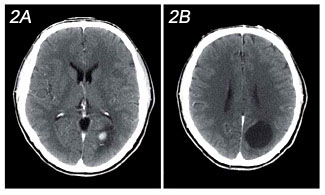

Figure 2: a,b

Contrast-enhanced CT matched images to Figure 1demonstrates homogeneous

enhancement of the medial mural nodule with no signifi cant enhancement of

the cystic component.

traumatic injury identified. Following the injection of contrast (Fig 2a,b),

there is identification of a 1 cm. enhancing nodule at the medial aspect of

the lesion.